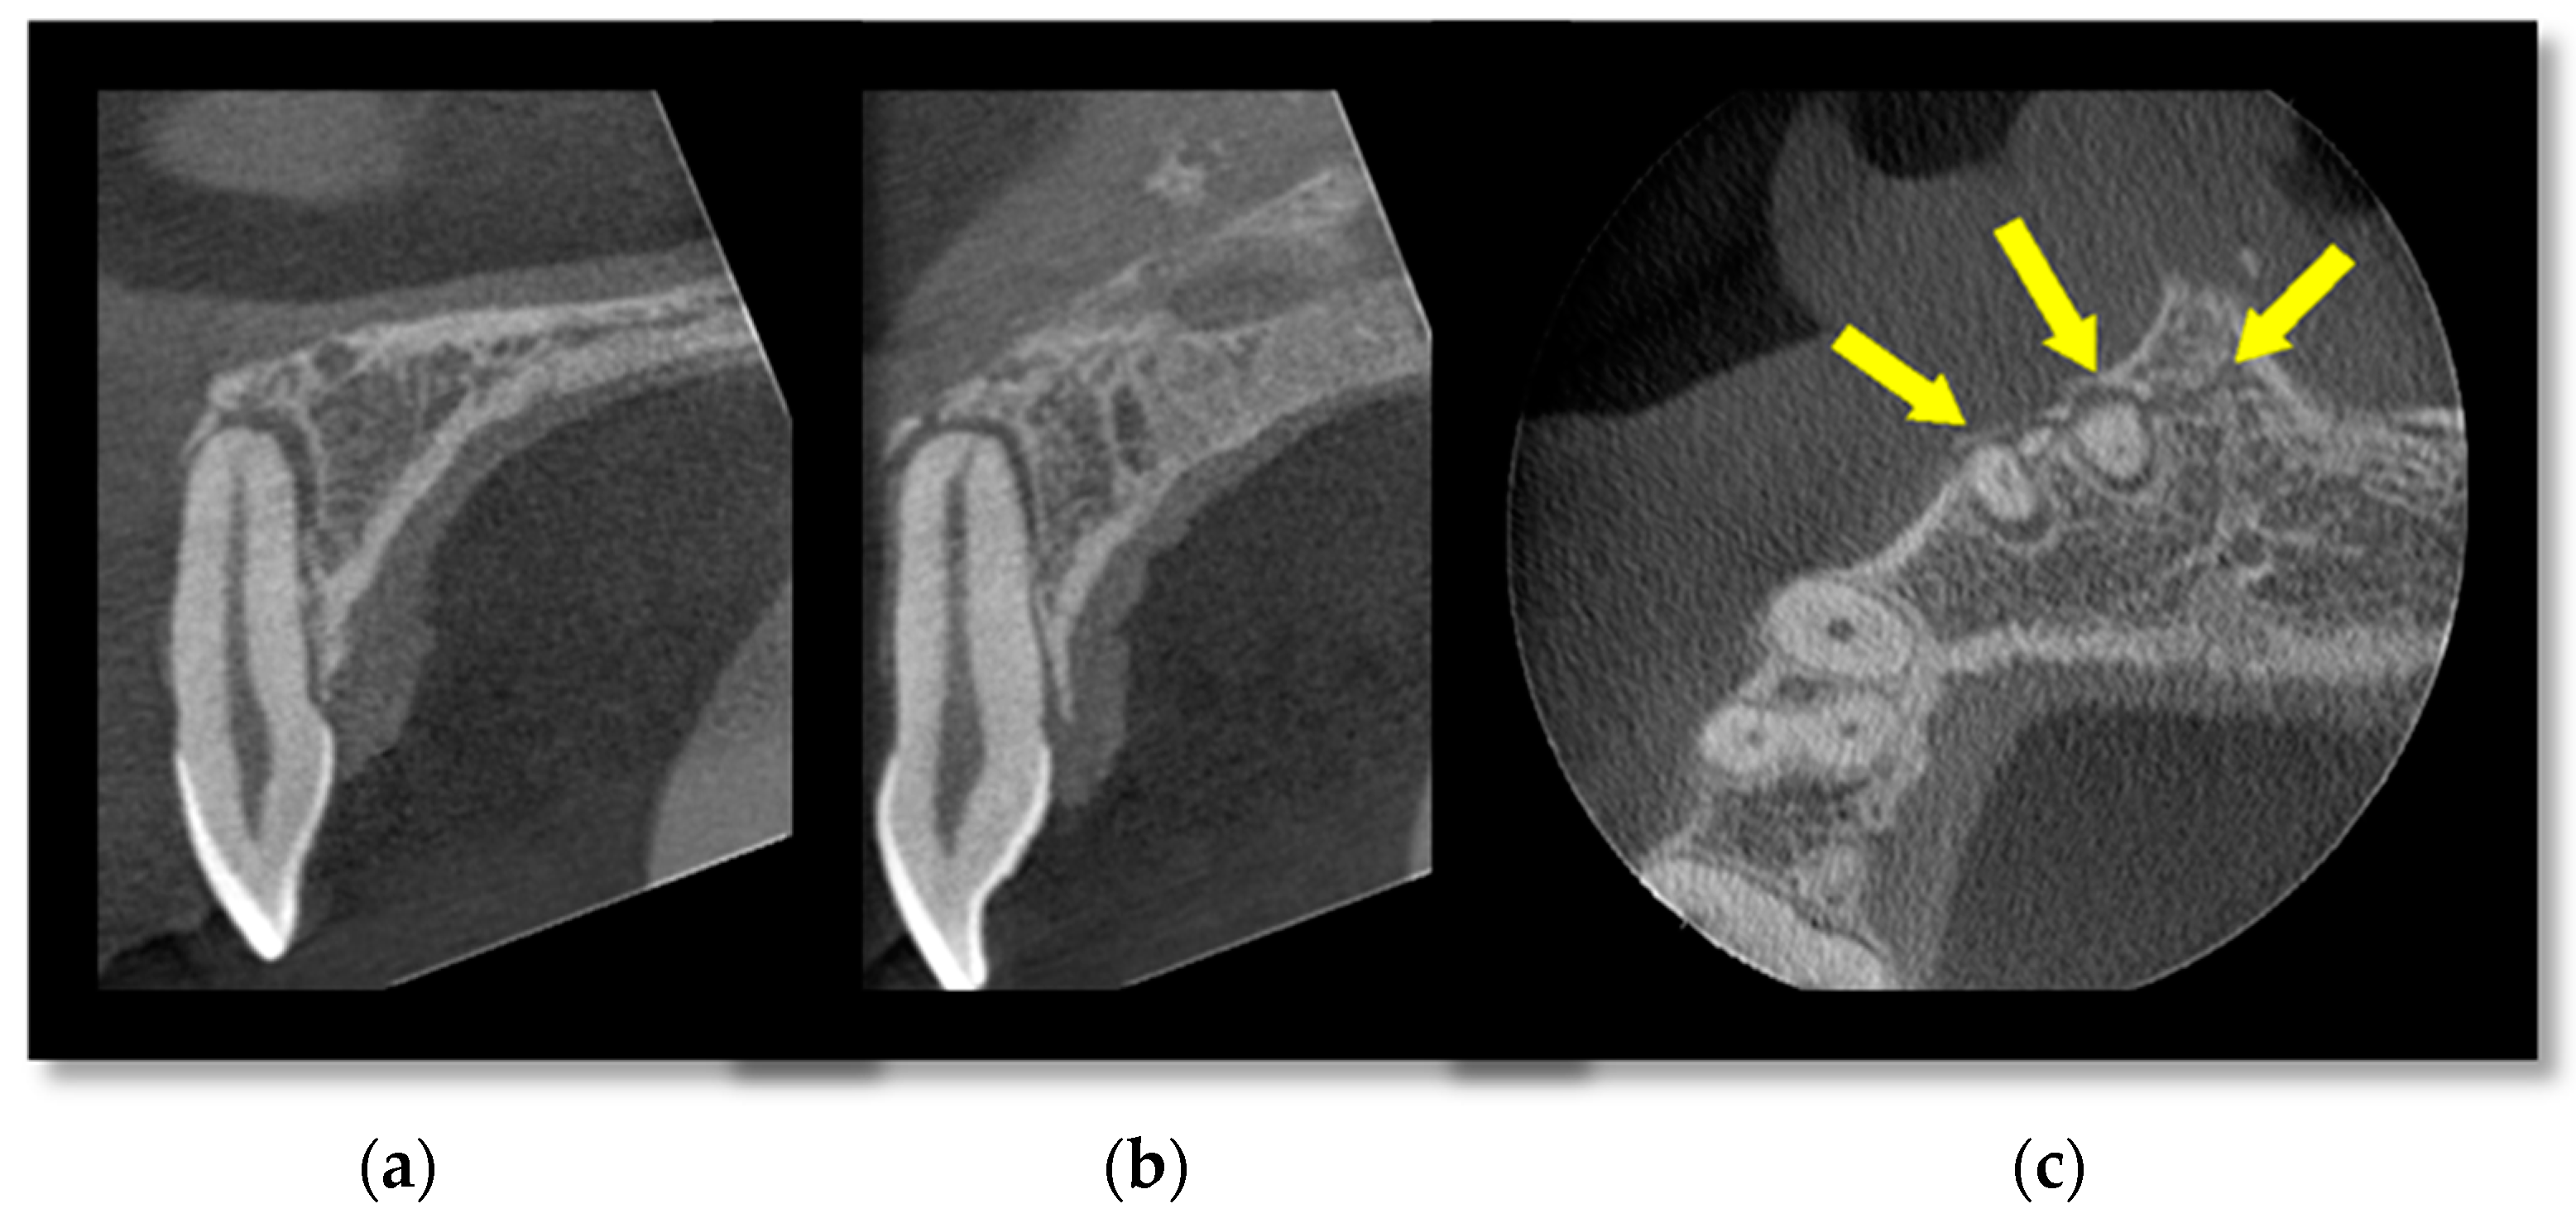

Figure 1 is a small-volume CBCT scan of the anterior maxilla showing luxation injuries of the UR1 and UR2 with an associated alveolar bone fracture that extends to the anterior nasal spine. This cross-sectional imaging allows for a more detailed assessment of the supporting structures of the teeth, which may influence management decisions. Figure 2 is an example of root fractures demonstrated on CBCT imaging that were occult on plain films.

Figure 1.

A small FOV CBCT of the anterior maxilla showing (a) luxation injury with (b) associated alveolar bone fracture (c) and extending to the anterior nasal spine demonstrated by the arrows.

Figure 2.

An (a) axial and (b) coronal section of a root-treated first maxillary molar tooth demonstrating a fracture through the furcation not evident on plain films. Arrows demonstrate the fracture.